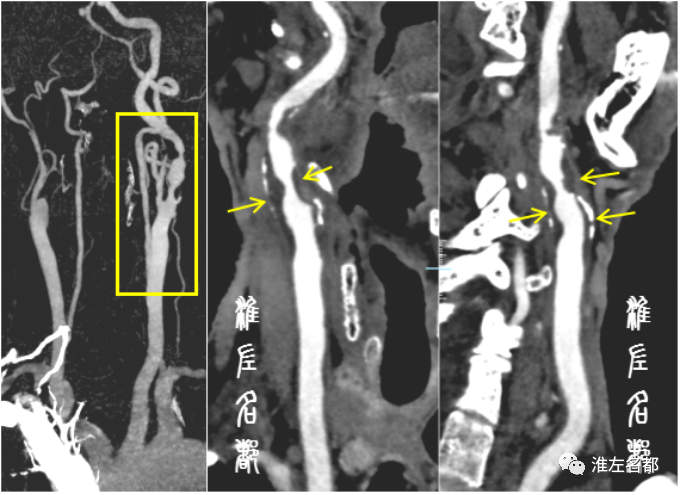

伴随科技发展,近半个世纪以来,多种先进技术,尤其是血管影像技术,被应用于脑血管病变的诊断评估,极大促进了该领域的发展。目前常规应用于脑血管病变评估的影像技术包括:DSA、CTA和MRA,这些技术主要通过显示血管腔的异常进行血管病变的评估,如狭窄、闭塞、动脉瘤、血管畸形等病变,其中以DSA的诊断准确性最高,常被奉为“金标准”,缺点是有创操作,有潜在风险。

对于一些管径相对粗大的颈部血管,颈部CTA原始图在管腔含碘高密度血液的衬托下,可显示一些明显的血管壁病变,如斑块组织、夹层壁内血肿和动脉炎性管壁增厚。但是,由于CT技术是基于物质原子序数和/或密度差异来形成对比度,一般只能识别显著高密度的斑块钙化,以及明显低密度的斑块脂质成分,而对于其他构成成分相近的软组织辨别能力差。对于颅内动脉病变,除了高密度管壁钙化外,就很难获取其他的颅内动脉管壁病变信息了。

根据好发部位和特征性影像改变,颈部血管疾病通常能获得准确的病因诊断;另外,常规的超声技术和CTA技术即可获取颈动脉管壁异常信息,并足以指导临床决策。因而,在目前的颈部脑血管病变的临床实践中,除了个别情况(医学研究,疑难病因诊断,或颈动脉闭塞介入再通治疗术前评估等),管壁高分辨MRI技术并不是常规需求。